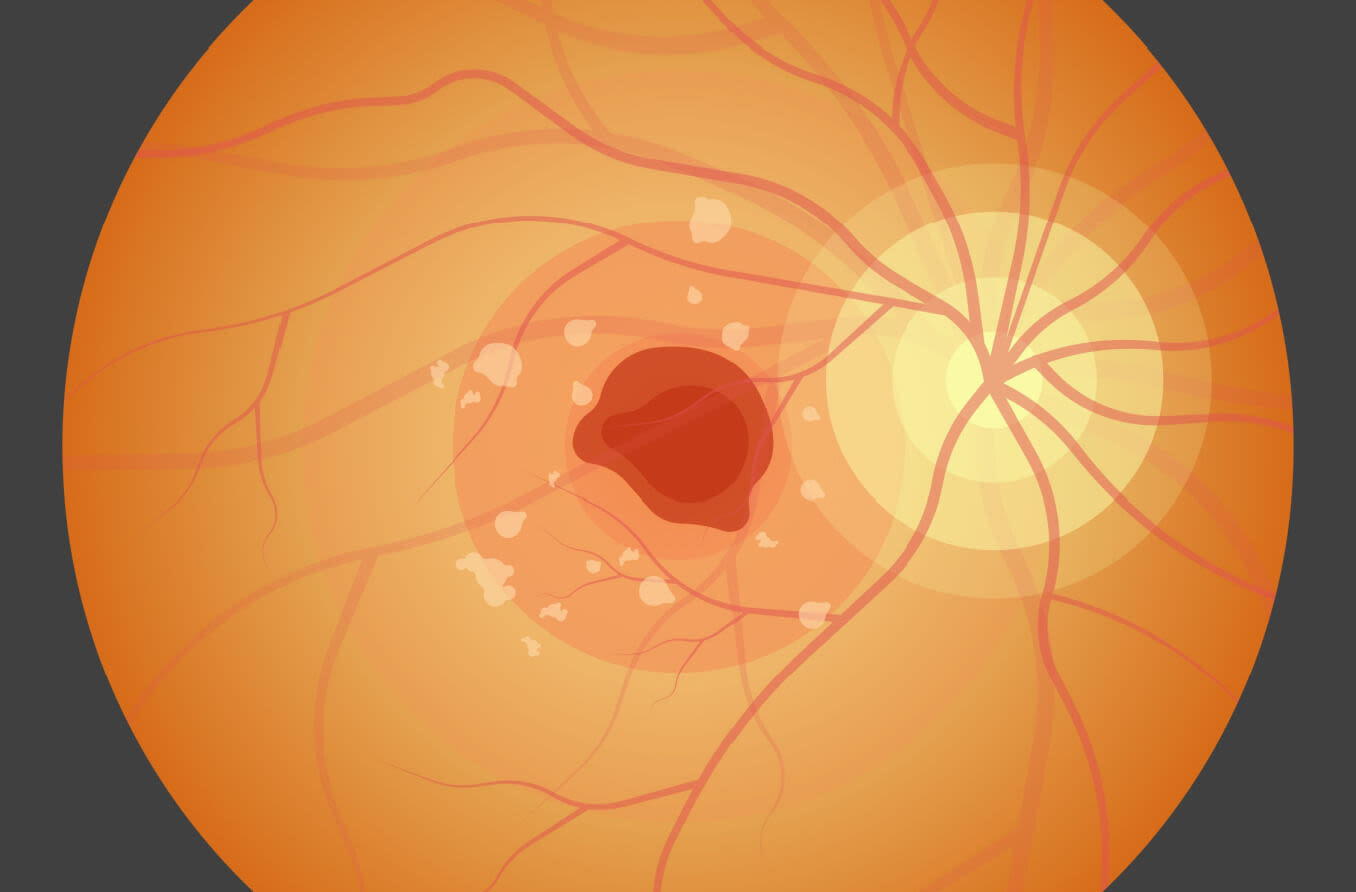

Stargardt hastalığı (fundus flavimaculatus)

Stargardt hastalığı tanısı retinanın (retinal pigment epitelyum) renkli veya dış örtüsünden soyulan bozulmaya başlamış dokuya ait küçük sarımsı noktaların varlığı ile konur. Progresif görme kaybı nihai olarak çoğu durumda körlüğe yol açar.

Stargardt hastalığının belirtileri, bulanık veya bozulmuş görmeyi, düşük ışık koşulları altında görememeyi ve tanıdık yüzleri seçmede zorluğu içerebilir. Stargardt’ın son aşamalarında, renkli görme yeteneği de kaybedilebilir.